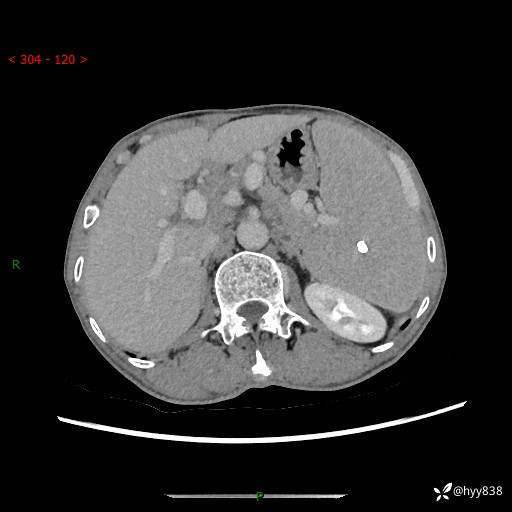

老年男性,脾大并脾脏弥漫粟粒状低密度,淋巴瘤 VS 肉芽肿 VS 血管瘤---结果公布

简要病史: 患者于3月前无明显诱因出现脾大,伴腹部轻微不适,具体不详,无腹痛、腹泻、腹胀,无头晕、头痛、乏力,无恶心、呕吐、呕血,无胸闷、气短、胸痛不适

上腹部CT平扫+增强